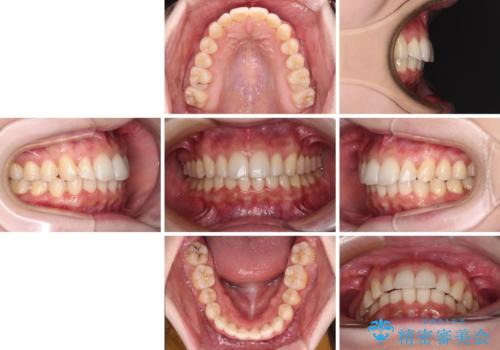

- 上の前歯が出っ張っている気がするとのことで来院された患者様です。

半年もせずにインビザラインを全く使用することができなくなってしまったので、治療開始から1年ほどでワイヤー矯正へ変更することとなりました。

ワイヤー矯正へ変更してからはあっという間に治療が進み、1年弱で終えることができました。